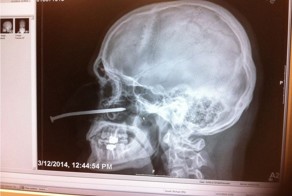

- Случайно забил себе в нос гвоздь